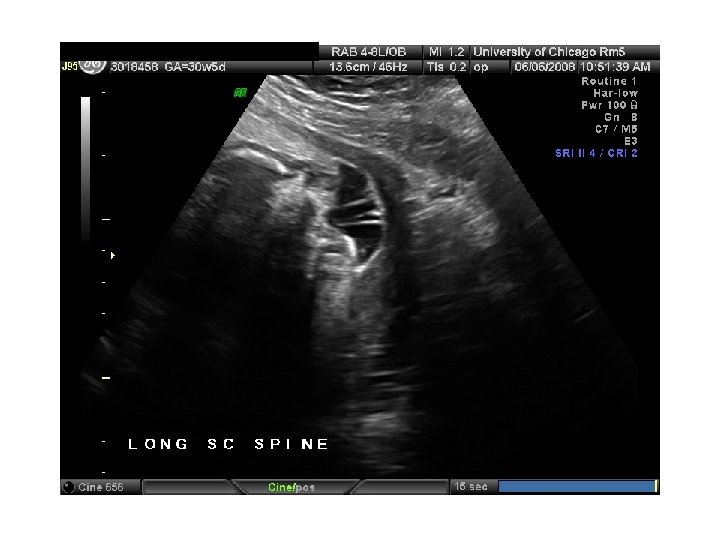

QUIZ What is Your Diagnosis? Case: Patient J. F. 30 years old, at 32 week gestation. Presented with the following pictures.

Answer: a) Trisomy 21 b) Non-immune Hydops c) Paravo virus Infection